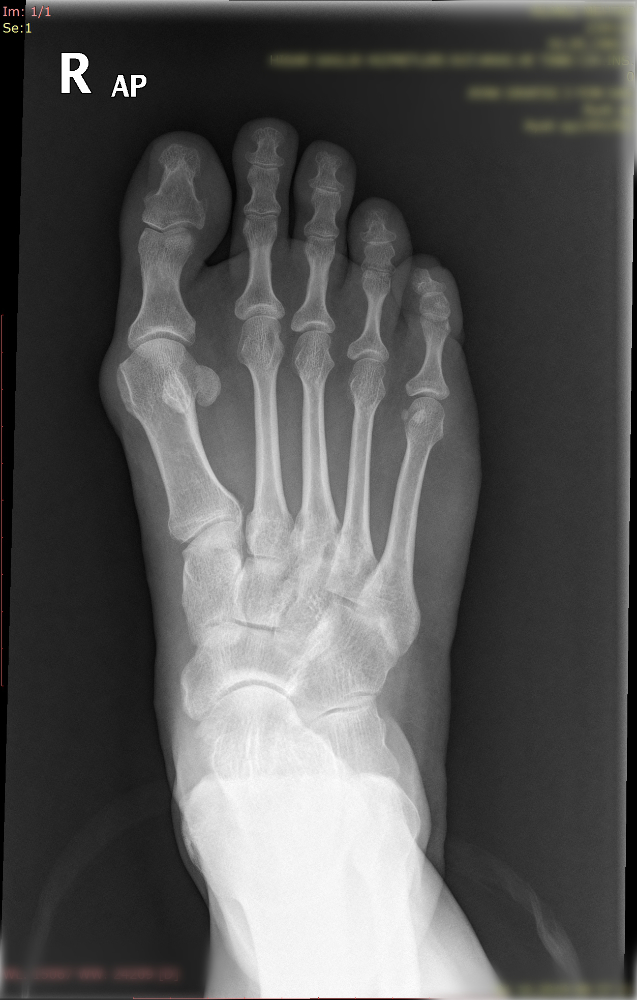

Halluk valgus ayak baş parmağının zaman içerisinde değişik nedenlerle eğilmesi ile ayak yan tarafında çıkıntının da eşlik ettiği bir rahatsızlıktır. Sıklıkla bayanlarda görülmesine rağmen erkeklerde ve çocukluk yaşlarında da karşılaşılmaktadır. Ayağın yan tarafında olan çıktı ve baş parmağın diğer parmakları itmesi ile ayakta şekil bozukluğu ve ağrı oluşur. Bu şekil bozukluğu kişinin ayakkabı giymesinde sıkıntılara neden olabilir.

Tedavisinde ayağın yük veriri pozisyonda çekilen grafileri üzerinde yapılan ölçümlerden sonra hastanın yaşı ve aktivite seviyesine göre kişiye özel planlanmaktadır. Erken dönemlerde ayakkabı modifikasyonu, parmak arası makarası ve gece ateli kullanılmaktadır. Cerrahi gerekliliğe hastanın deformitesinin büyüklüğüne ve hastanın taleplerine göre karar verilmektedir.

Aşağıdaki grafiyi öncesi sonrası şeklinde görmek için farenizi sağ sola hareket ettiriniz.

Yukarıdaki grafileri daha net ve büyük görmek için üzerine tıklayabilir. Sağ üst köşedeki + - tuşları ile daha da büyütebilirsiniz.